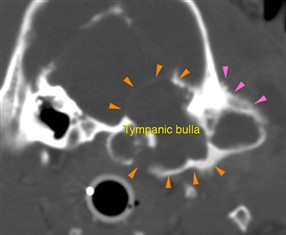

In this case, the patient could not open the mouth because of an aggressive expansile process affecting the left tympanic bulla, which was filled by non-contrast-enhancing material. The orange arrowheads show the thinned and expanded walls of the affected tympanic bulla, whilst the pink arrowheads highlight the solid periosteal reaction at the level of the left temporal bone.